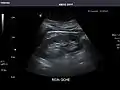

Right kidney

Kidneys: Right and left kidneys measure 11.5 cm and 12 cm in length respectively. No hydronephrosis. Small left lower pole kidney cyst.